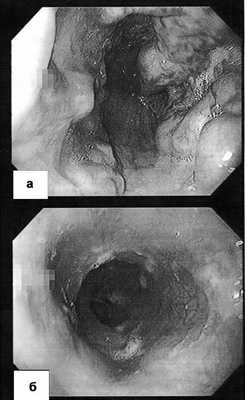

Из-за отсутствия признаков печеночной недостаточности при клиническом и лабораторном обследовании уже при поступлении наличие цирроза печени вызывало сомнения, было высказано предположение о внепеченочной портальной гипертензии, причиной которой явился тромбоз воротной вены вследствие заболевания крови. Мы выполнили эзофагогастродуоденоскопию, при которой в средней и нижней третях пищевода выявлены бугристые и извитые вены (варикозное расширение IV степени по классификации К. Paquet [2]), выступающие в просвет на 7-9 мм, с множественными эрозиями и «красными пятнами» - маркерами высокого риска кровотечения (рис. 2, а). Рисунок 2. Эзофагоскопия до (а) и после (б) мезентерикокавального шунтирования. Объяснения в тексте. Поэтому первым этапом мы выполнили эндоскопическое лигирование вен пищевода.

При эзофагогастродуоденоскопии перед выпиской отмечена хорошая редукция варикозно-расширенных вен пищевода (рис. 2, б), при компьютерной томографии через 1 мес после выписки визуализирован проходимый мезентерико-кавальный анастомоз (рис. 1, б). Во время контрольного осмотра через 3 мес состояние пациентки удовлетворительное, принимает кардиомагнил по 75 мг/сут, доза гидроксикарбамида снижена до 1000 мг/сут. Показатели гемограммы: Hb 107 г/л, эр. 5,04·10 12 /л, л. 9,6·10 9 /л, Ht 32,9%, тр. 505·10 9 /л, средний объем эритроцитов 65 фл, среднее содержание гемоглобина в эритроците 21,3 пг, лейкоцитарная формула не изменена.